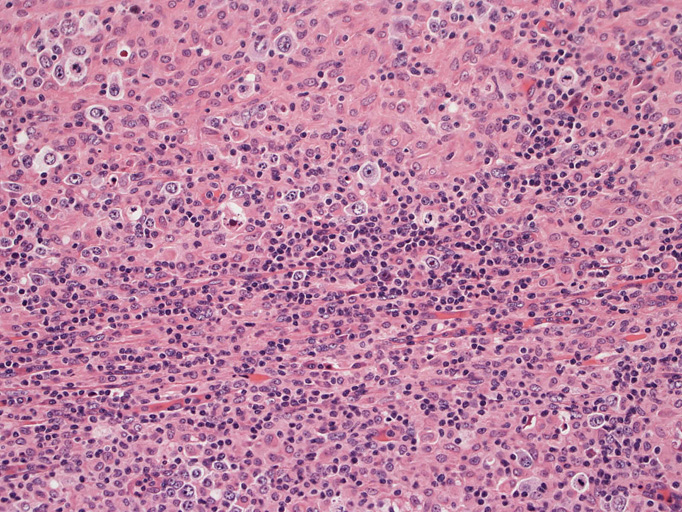

直径17mmの腫大したリンパ節。被膜は軽度線維性肥厚を示す。リンパ節の基本構造は失われ不明瞭な結節様構造が集蔟しているように見える。

結節構造内では, 好酸性細胞質をもつ組織球の増生を背景に大型異型細胞が散在性または集蔟して増殖している。被膜下にも線維化組織内にbizzarreな大型細胞が認められる。リンパ球は小型リンパ球が大型異型細胞を含む組織球性の結節辺縁に存在する。大型細胞は, centroblastic cellが多く, その他 Hodgkin cell-like cell, RS細胞様巨細胞, 腎臓型の核をもった細胞, 多型核の細胞など多彩な形態を示す。異型核分裂像をふくむ核分裂像が多い。

背景細胞はCD3+ Tリンパ球(CD8>CD4)とCD163, CD68陽性組織球。